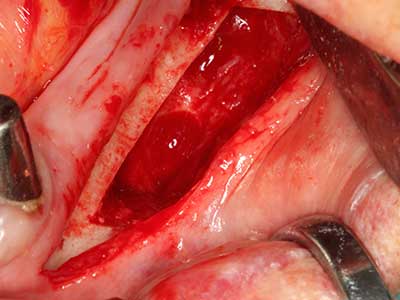

Fig. 18: Preparation of a cortical cover with the piezo bone saw (Piezomed, W&H).

Fig. 19: Surgical site after neurolysis and removal of osteoma.